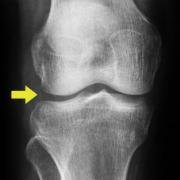

When one looks at an X-ray of the knee from the front, the normal knee shows an apparent gap between the long bones of femur and tibia. In fact this gap is filled by the menisci - but because they are radiolucent the X-ray 'does not see them' and the gap just looks empty.

Before such bow-leggedness or knock-knees are apparent, the astute radiologist usually picks up the fact that the gap in a weight-bearing X-ray is diminished on the relevant side, and this gives a good indication that the knee is moving into a danger zone where joint cartilage breakdown might result and arthritis ensue. In that case, the surgeon may contemplate osteotomy surgery to unload the joint on that side, or meniscus replacement to try to restore the original anatomy.